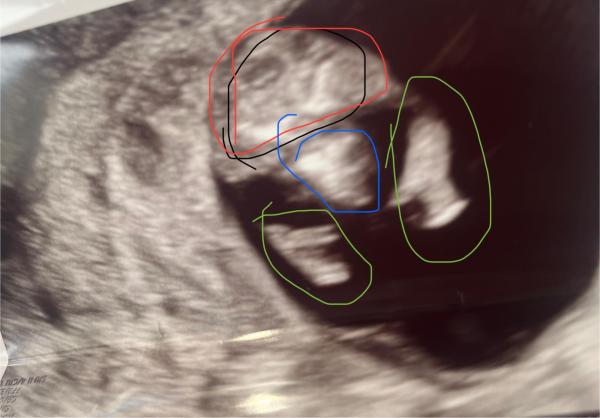

Hallo an alle Schwangeren und Mamis mit Erfahrungen. Ich habe in der 11ssw ein Ultraschall Bild von meinem FA bekommen. Er hat einen Querschnitt geschaltet und genau bei dem Baby zwischen den Beinen geschallt. Ich habe dieses Bild auch mitbekommen mit einem grinsen 😁 Wir kenn ihn schon ziemlich lange ich bin seit 17 Jahren schon bei ihm er hat alle 3 Schwangerschaften begleitet und ist eigentlich sehr erfahren. Dieses  Bild macht mich total irre 😵‍💫😅 und dann noch dieses grinsen. Eigentlich denke ich in dieser Woche ist es unmöglich das Geschlecht zu erkennen. Aber vil hat jemand von euch ein ähnliches Bild und schon ein outing. Oder schon Kinder bei denen so ein ähnliches Bild entstanden ist. Teilt gerne eure Erfahrungen ich bin über jede Antwort dankbar. Villeicht ist jemand grad in der selben Situation und man kann gemeinsam dem Geschlecht entgegen hibbeln😁

Hey, dieses Bild soll ein Querschnitt sein, der genau zwischen den Beinen zeigt. Ich habe diesmal eingezeichnet. Vielleicht ist es dann besser zu verstehen. Rot ist Bauch grün die Beine blau das Geschlecht.